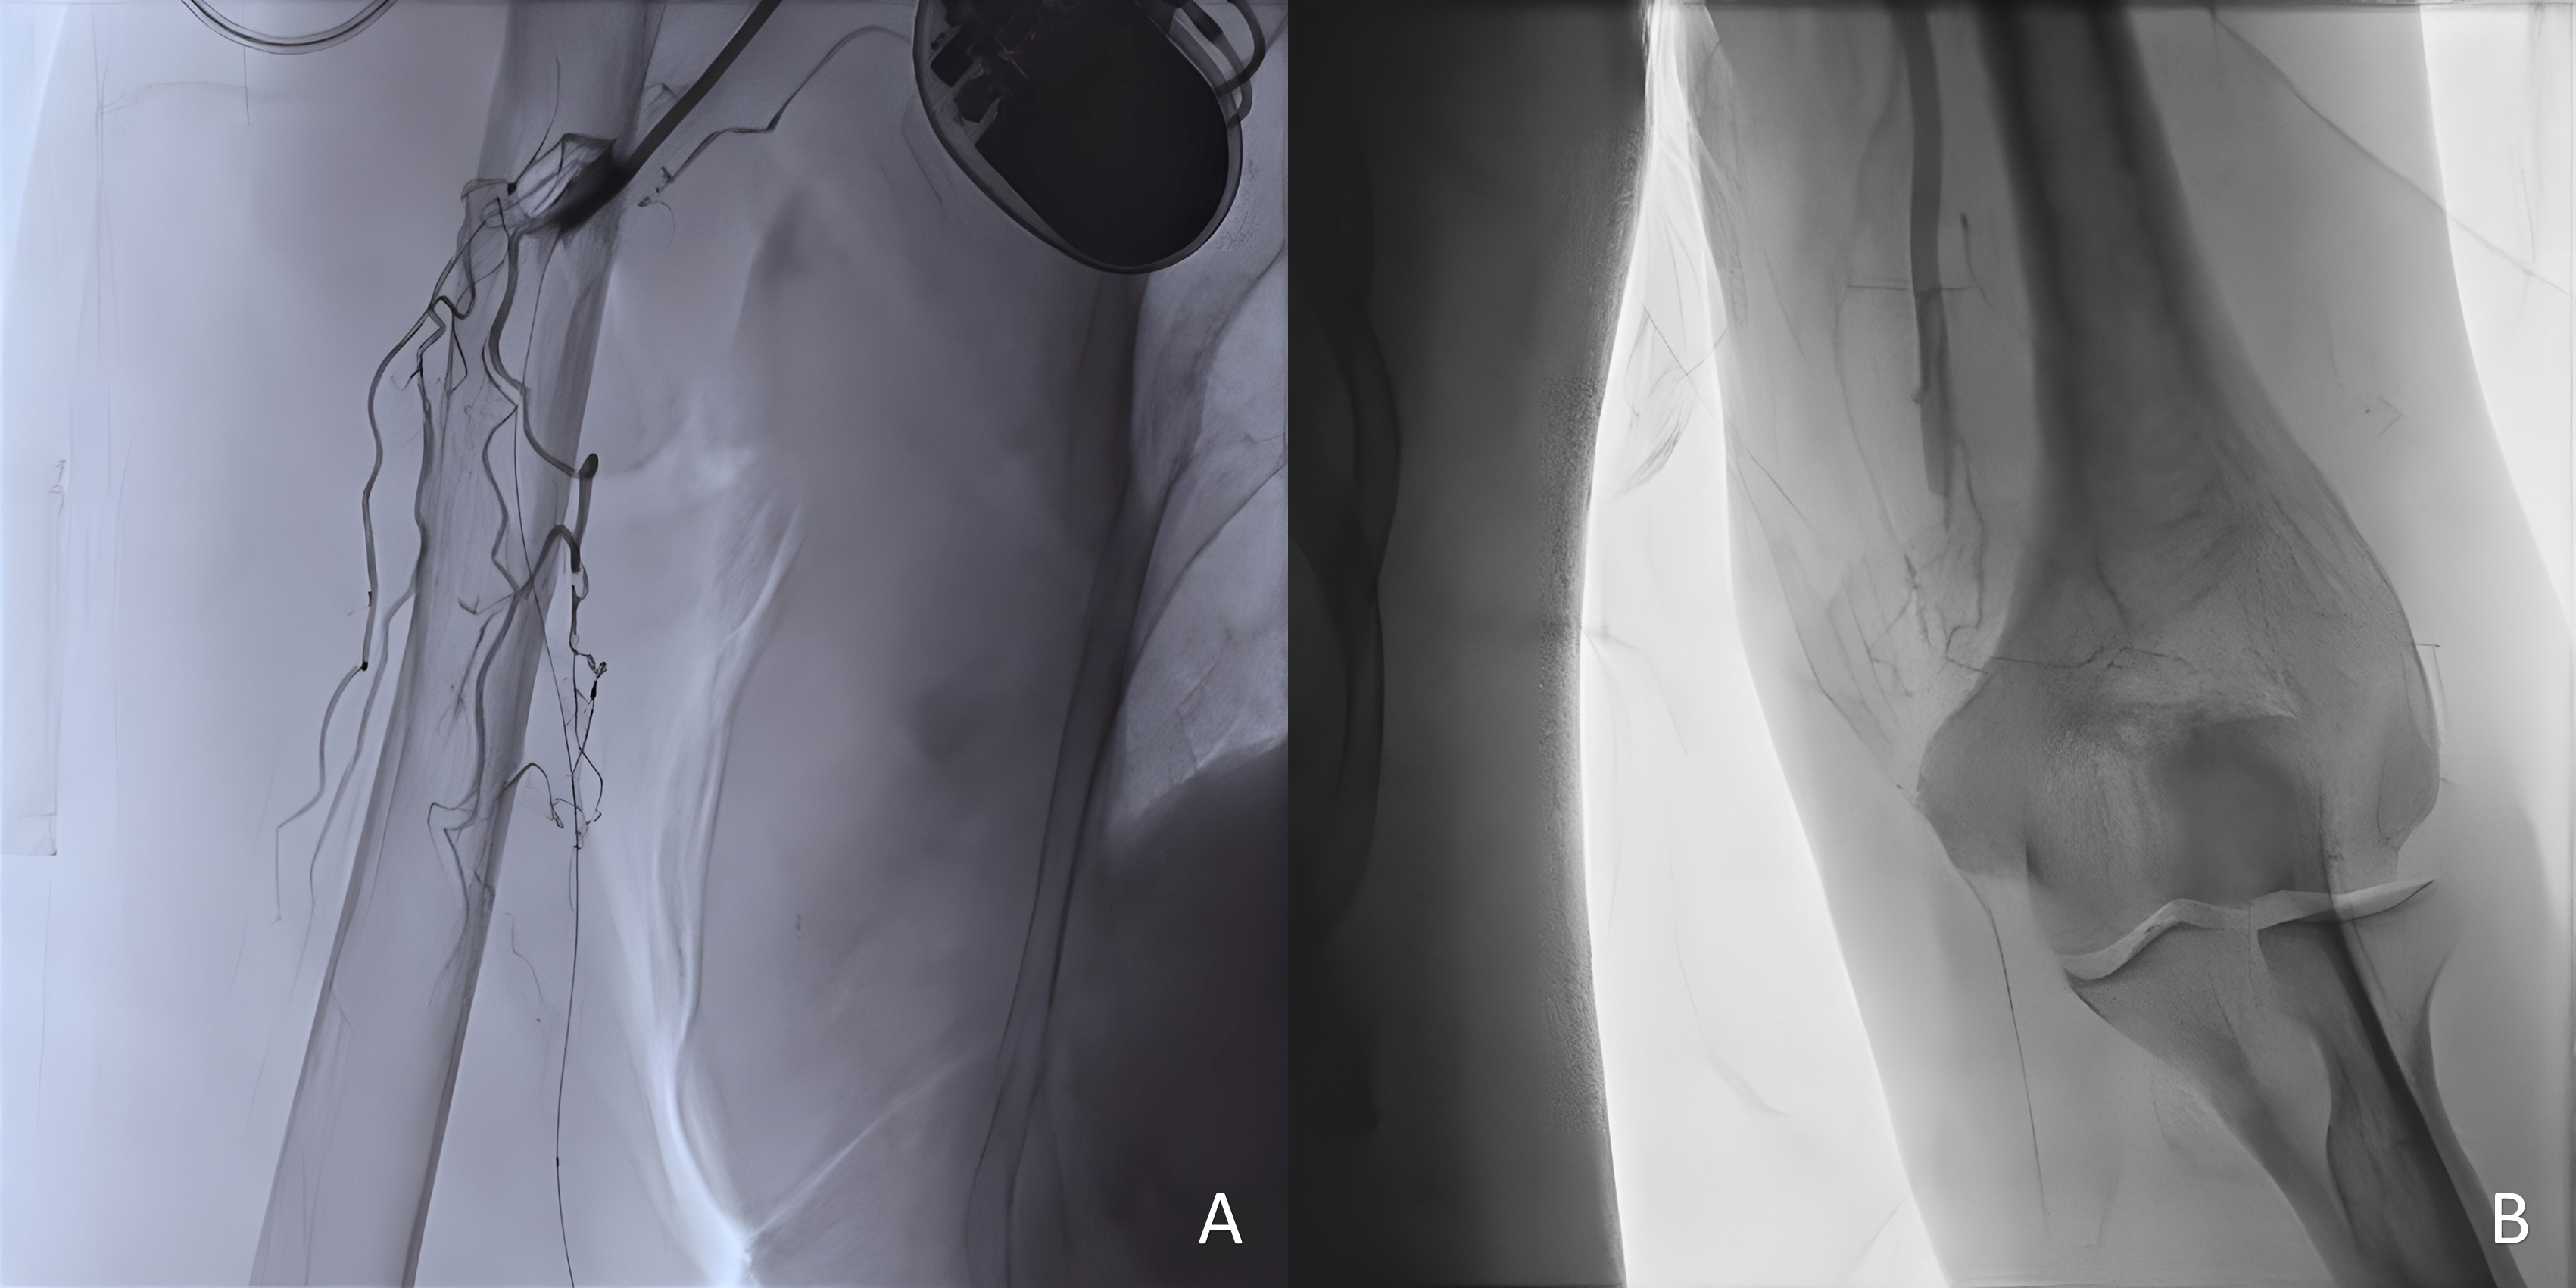

AP-frontal angiography in all of the cases confirmed mid-distal brachial artery occlusion, alongside an existing collateral vessel, with a difference in the affected arm side; left (Figure 4A) and right (Figure 4B).